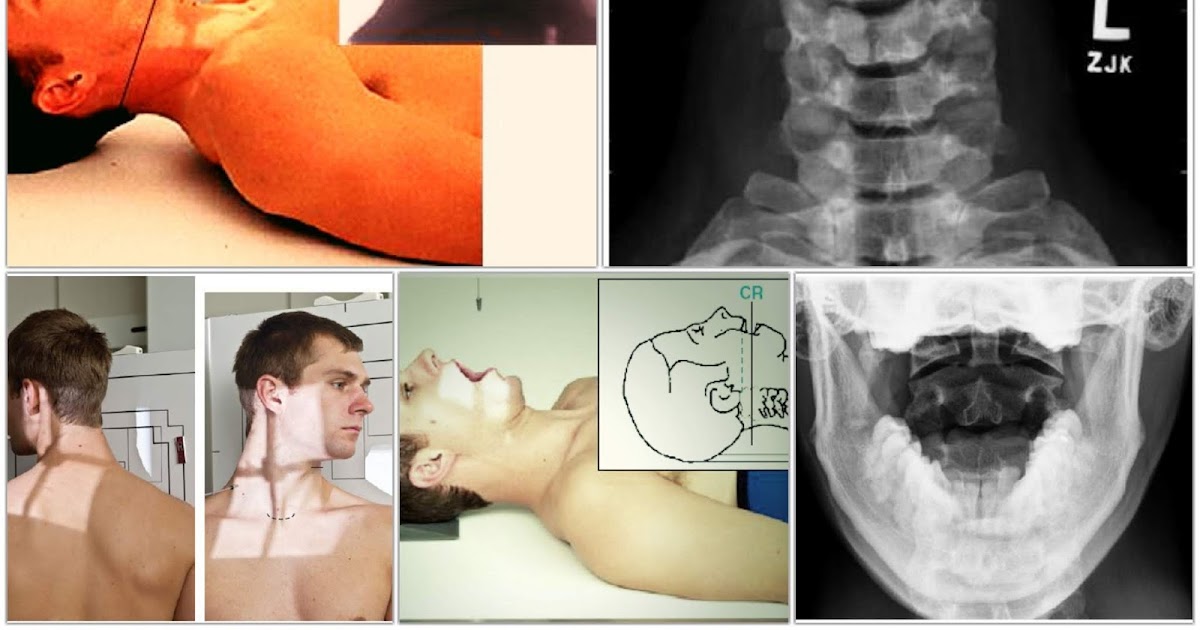

Cervical Spine or Neck Xray Radiography RadTechOnDuty Radiology Patient Positioning Correct positioning isn’t just crucial for diagnostic accuracy and. The purpose of this article is to provide a review for the radiology nurse on the essential elements of patient positioning for. Standard nomenclature is employed with. Patient positioning is crucial for medical imaging as it ensures optimal visualization of anatomical structures, reduces artifacts, and improves. The importance of appropriate patient. Radiology Patient Positioning.